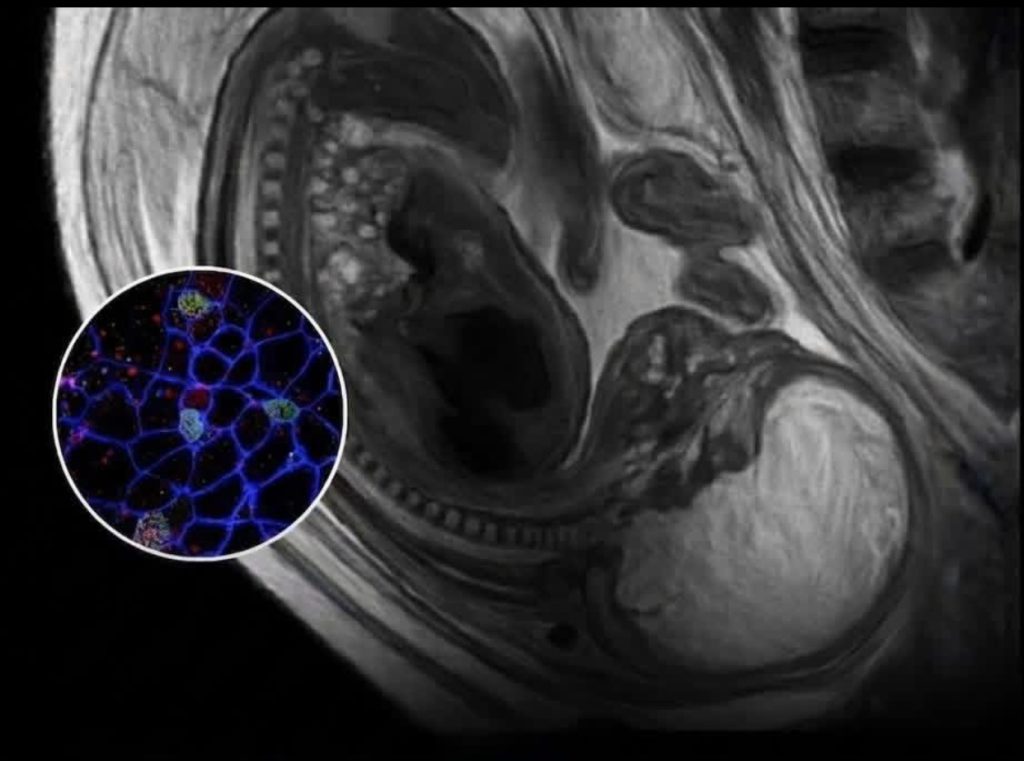

هذه الظاهرة تُعرف علمياً باسم “الخيمرية الدقيقة” (Microchimerism). إليك التفاصيل ببساطة:

- تبادل الخلايا: أثناء فترة الحمل، يحدث تبادل مستمر للخلايا بين الأم والجنين عبر المشيمة في الاتجاهين.

- خلايا الجنين في الأم: تنتقل خلايا الجنين إلى جسم الأم وتستقر في أعضاء مختلفة (كالقلب والكبد والدماغ) وقد تبقى لعقود بعد الولادة.

- خلايا الأم في الجنين: الأهم بالنسبة لسؤالك هو أن خلايا الأم تنتقل أيضاً إلى الجنين وتستقر في أنسجته.

- البقاء “للأبد”: أظهرت الأبحاث أن هذه الخلايا الأبوية (Stem cells أو خلايا مناعية) يمكن أن تبقى في جسم الإنسان وتتطور وتتكاثر معه طوال حياته، حتى بعد بلوغه سن الرشد بعقود.

بالتالي، الجملة المذكورة في الصورة: “خلاياها تبقى داخل جسدك للأبد” هي صياغة عاطفية لكنها تستند إلى حقيقة بيولوجية مثبتة، حيث يحمل كل إنسان في داخله، حرفياً، جزءاً حياً من والدته. # مجلة إيليت فوتو آرت